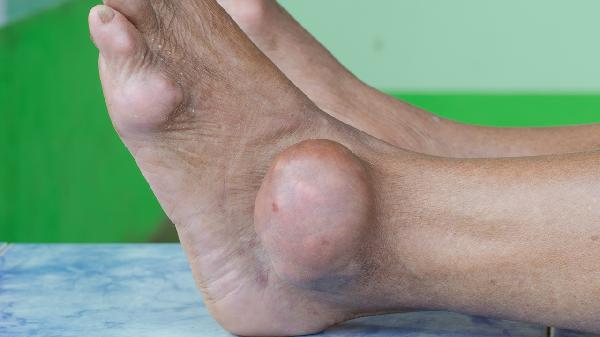

長(zhǎng)期穿窄頭鞋或高跟鞋可能導(dǎo)致第一跖骨內(nèi)翻,形成拇外翻。關(guān)節(jié)畸形會(huì)引發(fā)持續(xù)性鈍痛,行走時(shí)加重,可能伴隨大腳趾內(nèi)側(cè)骨贅增生。輕度可通過(guò)矯形器緩解,嚴(yán)重時(shí)需行截骨矯形術(shù)。常用藥物包括雙氯芬酸鈉緩釋片、塞來(lái)昔布膠囊等抗炎鎮(zhèn)痛藥。

高尿酸血癥引發(fā)尿酸鹽沉積在跖趾關(guān)節(jié),表現(xiàn)為夜間突發(fā)劇痛、皮膚發(fā)紅發(fā)熱。急性期需限制嘌呤攝入并使用秋水仙堿片,慢性期可服用非布司他片降尿酸。發(fā)作期間建議抬高患肢,避免關(guān)節(jié)負(fù)重。